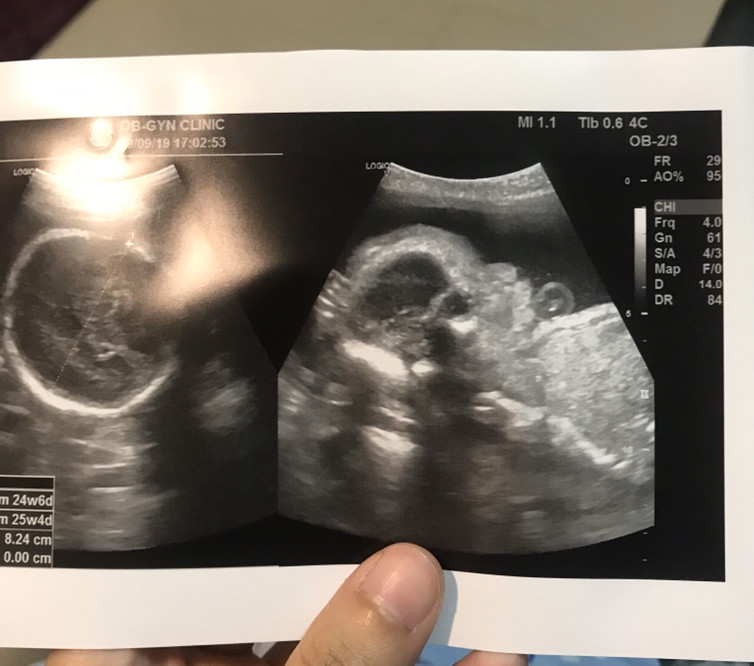

5 เดือนค่ะ 😍😍